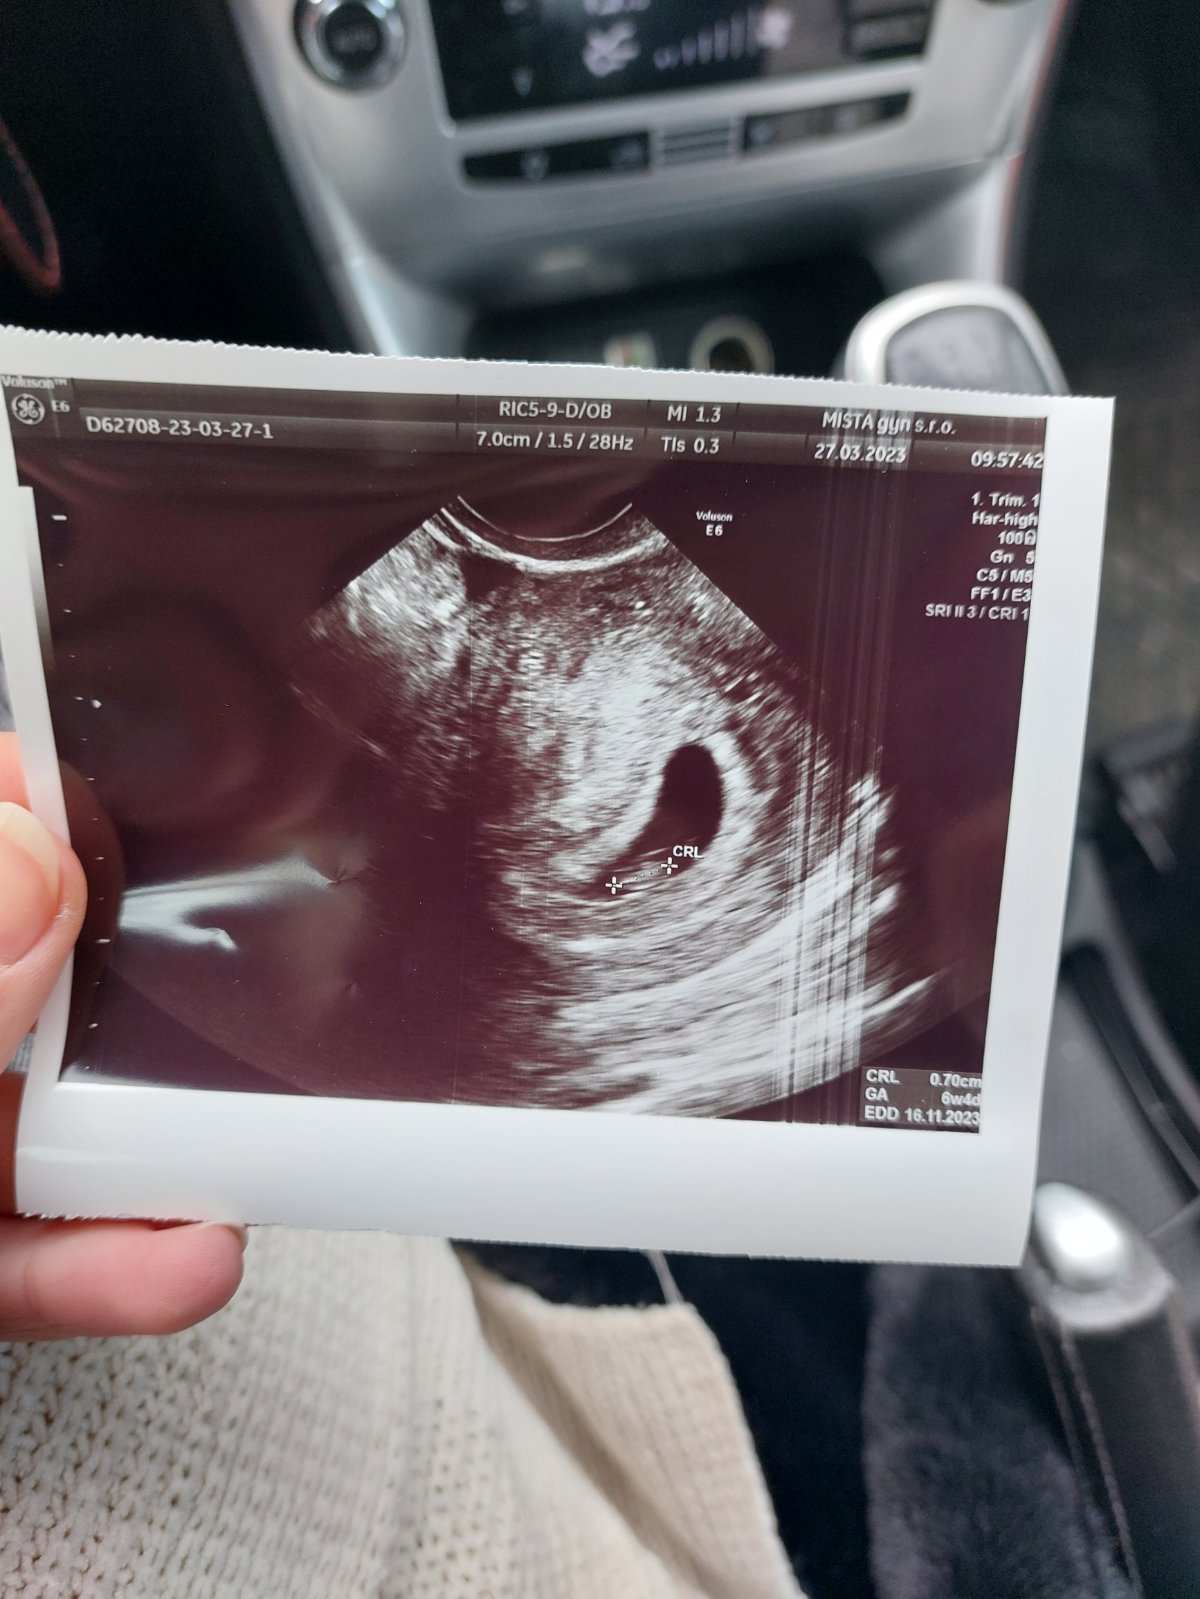

Mala by som byť v 8. týždni (7t + 3d) podľa výpočtu poslednej menštuácie, ktorá bola 3.2.2023. Na snímke od doktorky je však 6. týždeň plus 4 dni.